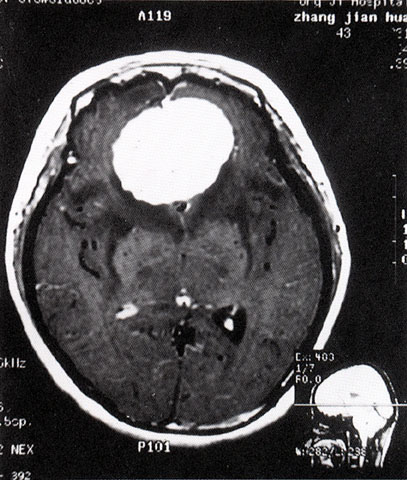

FH1058 脑膜瘤(MRI)

光盘检索编码 FH1058 函授作业图编号 1058

图 名 脑膜瘤(MRI)

导 学 阅图分析

讨 论 题 阅图分析